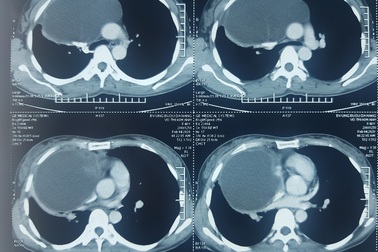

Khó thở, đau ngực vì khối u to như quả cam chèn ép tim phổiChiều 18/9, Bệnh viện ung bướu Đà Nẵng cho biết, vừa phẫu thuật thành công cho một bệnh nhân bị khối u trung thất lớn chèn ép tim, phổi.